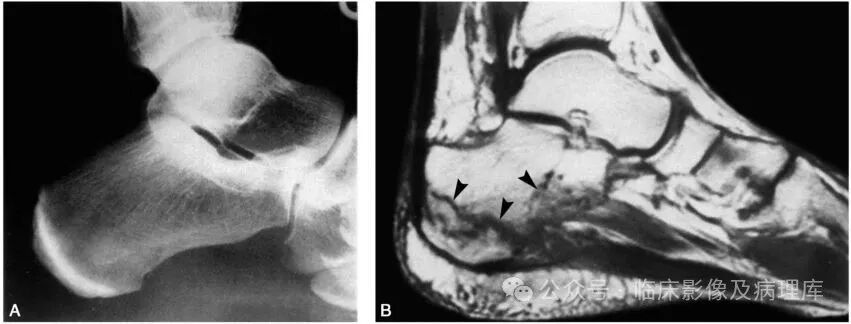

女,52岁。外伤后足跟疼痛。A.X线平片,左跟骨未见骨折线;B.足矢状位,MRI T1WI,显示跟骨体及跟骨结节上部骨折线呈低信号强度(黑箭头);C.T2WI跟骨骨折线呈高信号强度和中低信号强度(黑箭头)

亦称骨挫伤(bone contusion),为骨小梁微骨折,骨髓内沿骨折线出血,X线检查不能显示出骨折线。隐性骨折多发生于松质骨内,骨折后2~3周X线检查或CT扫描偶可显示骨折裂缝。MRI可表现为骨髓水肿,T1WI为低信号,T2WI脂肪抑制像为高信号强度。